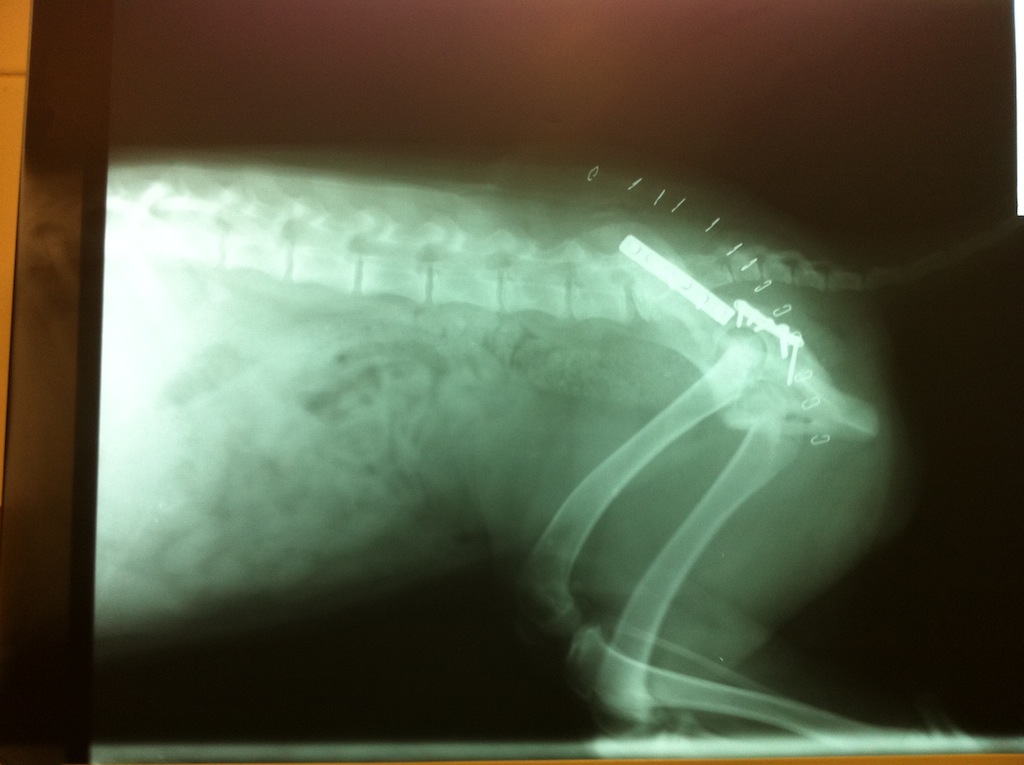

DANA sufrió un accidente. Está recién operada, guardando reposo y empezando rehabilitación en su casa de acogida. Desde aquí queremos agradecer a todas las personas que os habéis implicado en su caso, en especial a Mascoteros. Dana, ¡ponte buena pronto!